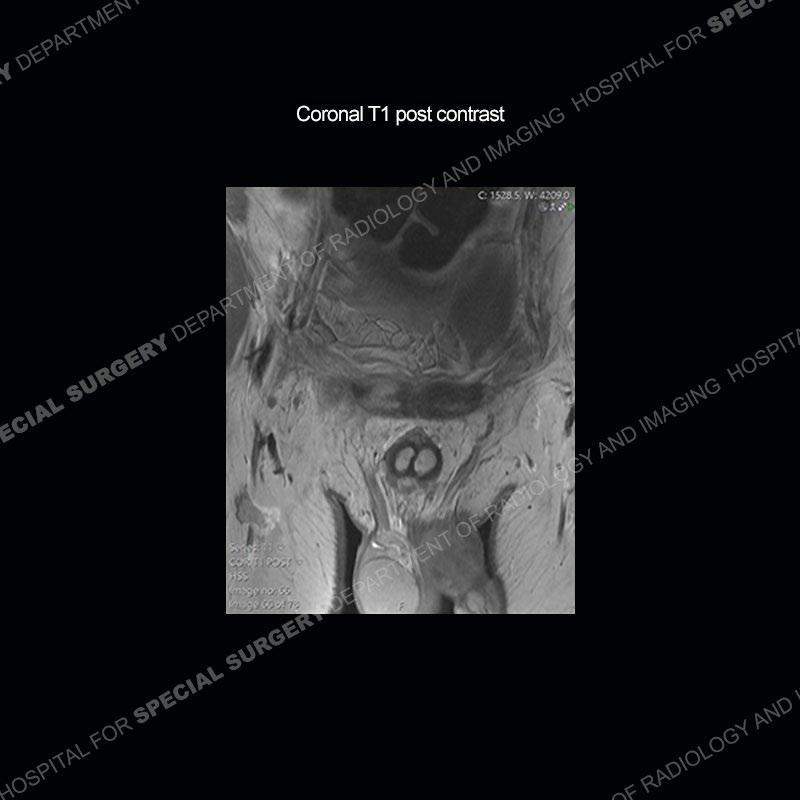

Subsequent MRI in a very short time interval shows markedly increased abnormality of the ramus and increased edema and “mass” of the soft tissue. Post contrast imaging shows multiple, rim enhancing collections of the soft tissue and similar albeit less conspicuous enhancing collection of the ramus.

The repeat MRI, with the marked degree of increased abnormality of the bone and soft tissue shifted the diagnosis to a high degree towards infection. Even the most aggressive of neoplasms would not have that the degree of change in a 3-day time span. The CT study was shown before the repeat MRI but actually occurred just after the repeat MRI. It helped confirm the destructive process of the ramus and particularly the abnormal architecture along the inferior margin. The patient went on to have a CT guided aspiration of one of the soft tissue collections with 4cc of purulent fluid obtained. A surgical irrigation and debridement of the bone and soft tissue was performed. A PICC line was placed and the patient is currently undergoing IV antibiotic treatment with a possible repeat irrigation and debridement.